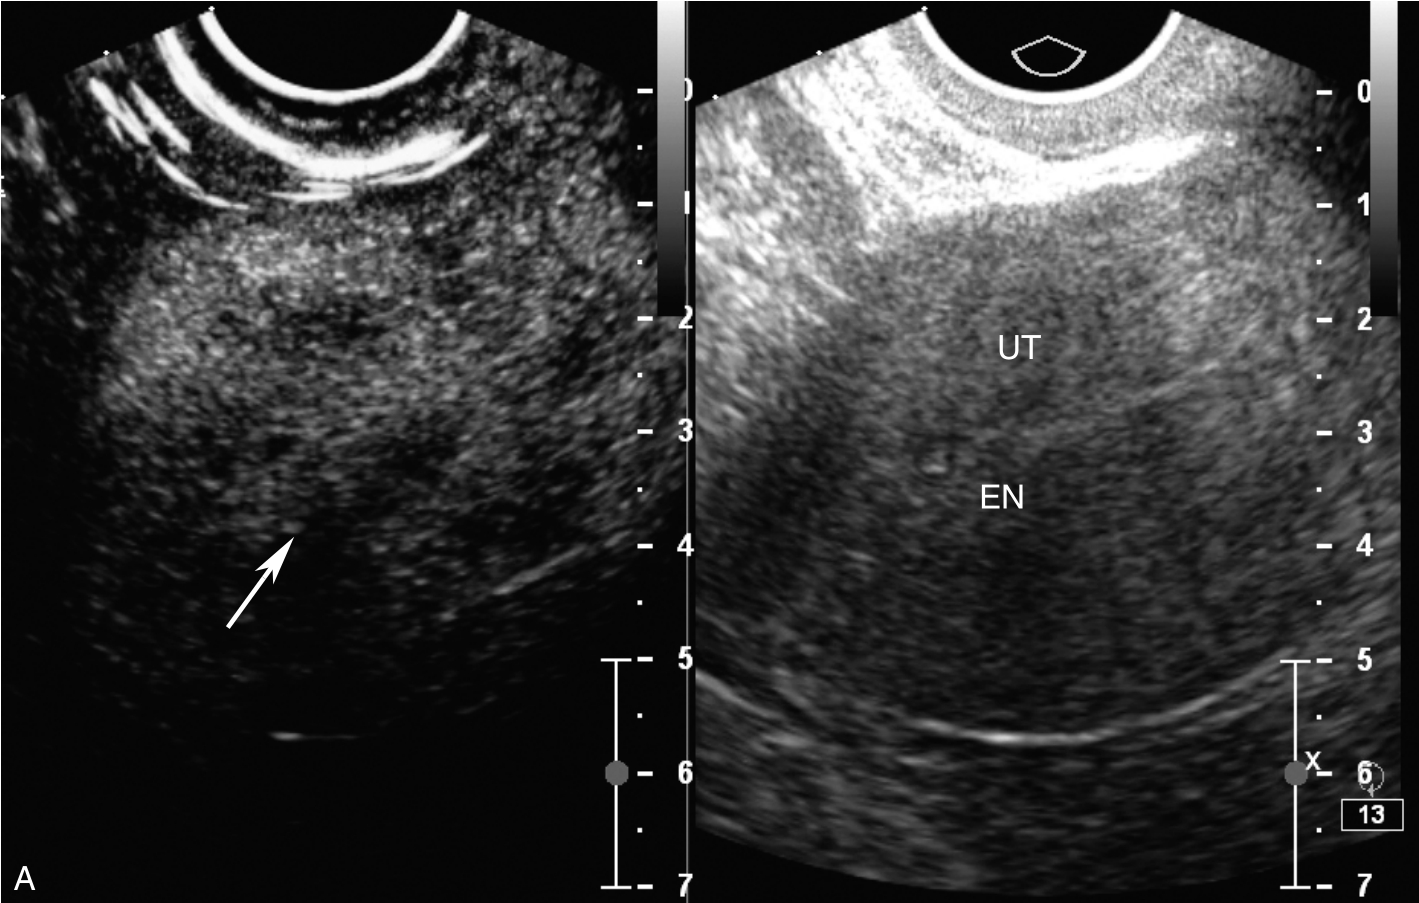

CT检查(入院当天)见图3-12-1,右侧闭孔区淋巴结稍增大,大血管旁未见增大淋巴结;右附件区稍增厚,可见小囊状影。

图3-12-1 盆腔CT图像

A.盆腔子宫底横切面;B.盆腹腔子宫矢状面。UT:子宫。